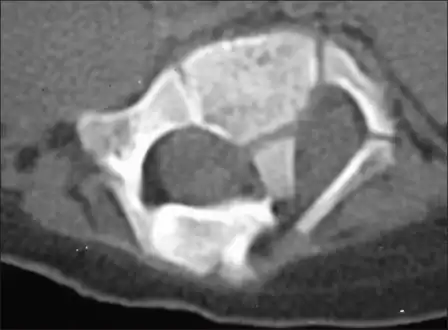

- Computerized tomography - shows diastematomyelia with a large intraspinal bony bar at L2–L3 vertebral level